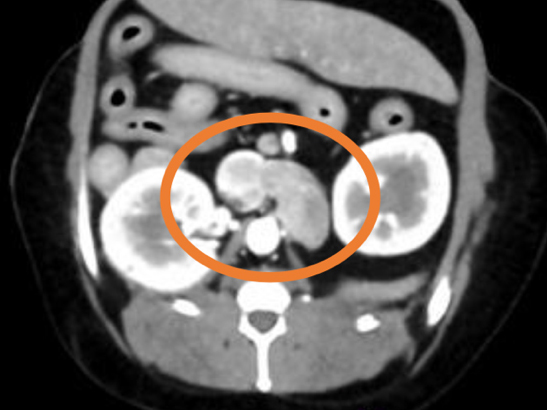

膀胱結石の精査目的で他院にてCT検査を実施したところ、左副腎に腫瘍性病変が認められ、後大静脈への浸潤も確認されました。 これを受けて、手術目的で当院を受診されました。 当院にて褐色細胞腫摘出術を実施し、術後は体調良好であったため、術後4日目に退院されました。

手術前のCT検査にて腫瘍の浸潤・転移チェックを実施